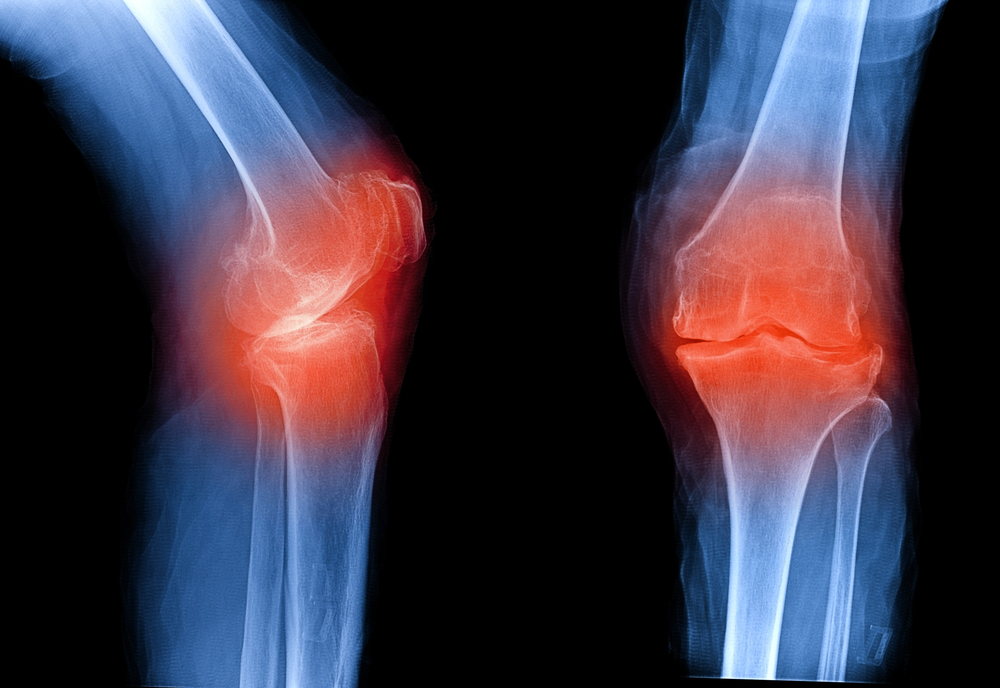

Предварительный диагноз устанавливается на основании жалоб больного и данных объективного осмотра (деформация сустава, болезненность при пальпации, ограничение объема движений, крепитация). Для подтверждения диагноза проводится рентгенография (на снимке сустава заметно сужение суставной щели, краевые костные разрастания – остеофиты, на более поздней стадии – уплощение суставной поверхности кости).